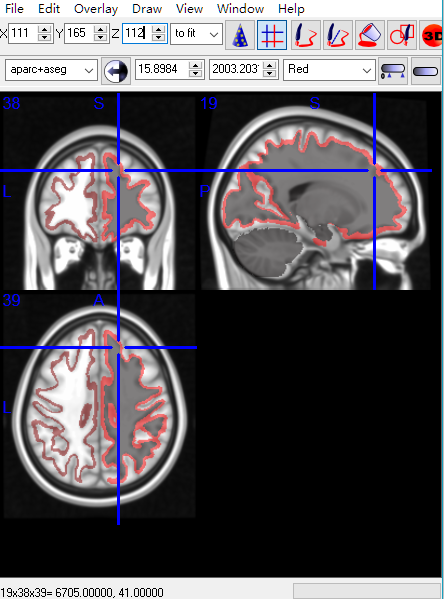

1)画图确认下ROI5.nii中的ROI是不是在你想要的地方,这一步很多软件都可以轻易完成。

临时使用一下上面得到的变换矩阵,做个图看看是不是经过变换的ROI是不是想要的位置。

同样可以做个图看看变换的结果lh.fsaverage.ROI5.mgh是不是在想要的位置。

直接把aparc+aseg.nii map到mni152_T1上

看起来是没问题的